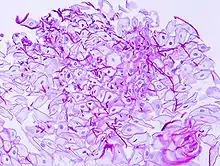

Une candidose est une infection fongique causée par des levures du genre Candida. Le terme peut désigner tout une gamme de manifestations pathologiques ayant pour facteurs ces champignons levuriformes. C'est l'une des principales infections fongiques humaines dans le monde.

Candida albicans (responsable du « muguet blanc »), l'espèce la plus fréquente, fait partie de la flore habituelle de l'oropharynx ou du tube digestif, et peut aussi être présent en faible quantité dans la flore vaginale normale.